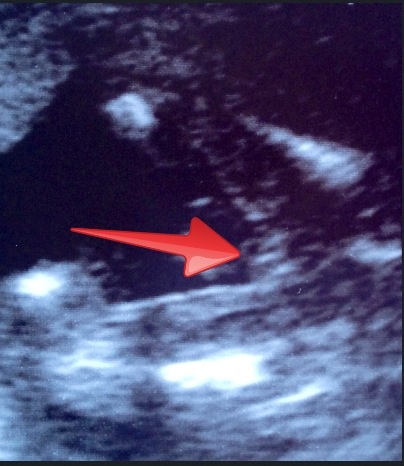

My confirmed girl pics at 12 weeks, 15 weeks and 17 weeks...

Attachment 13333